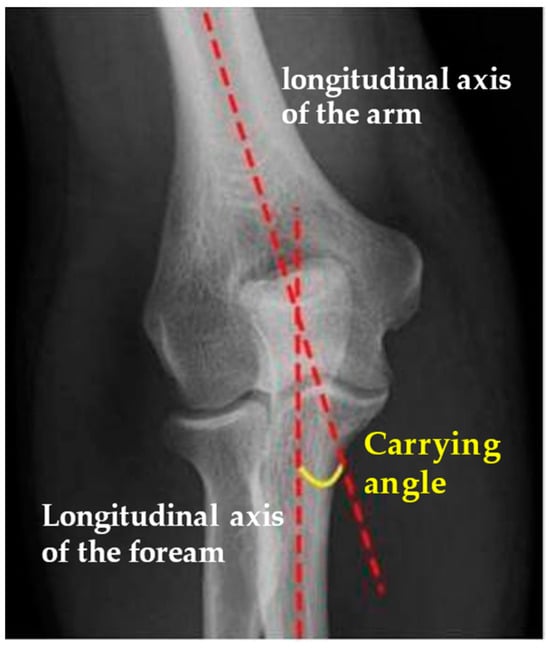

| Carrying Angle | 12.3° | 4.28 | 5–22° |

| Contralateral Carrying Angle | 12.3° | 3.87 | 5.9–20° |